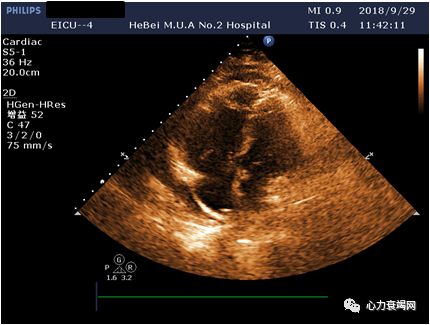

(ECMO第1天,9.29)

EF20%

➤ 心功能差,心脏基本不动

课件提供资料:本例患者以压榨性胸痛发作3天于9月29日转入,入院时Bp 84/46mmHg,心电图示S1QⅢTⅢ、V5导联R/S<1,cTnT 0.144ng/ml,NT-pro-BNP6177.7 pg/ml,D二聚体11.68mg/L,Lac 7.7mmol/L,入院考虑冠心病心梗,肺栓塞?肺癌?初步治疗后(不详)胸闷胸痛无好转,血压持续低,心电不稳定,PaQ2降至87mmHg,PaCO2及乳酸升高,即予ECMO、液体负平衡、抗凝抗血小板并加予”左西孟旦”治疗,逐渐血压上升,氧合改善,一周后转普通病房治疗,10月9日又突发胸闷气短,后续治疗未列出。入院前淋巴结活检提示:转移性低分化腺癌,CTPA示肺栓塞。